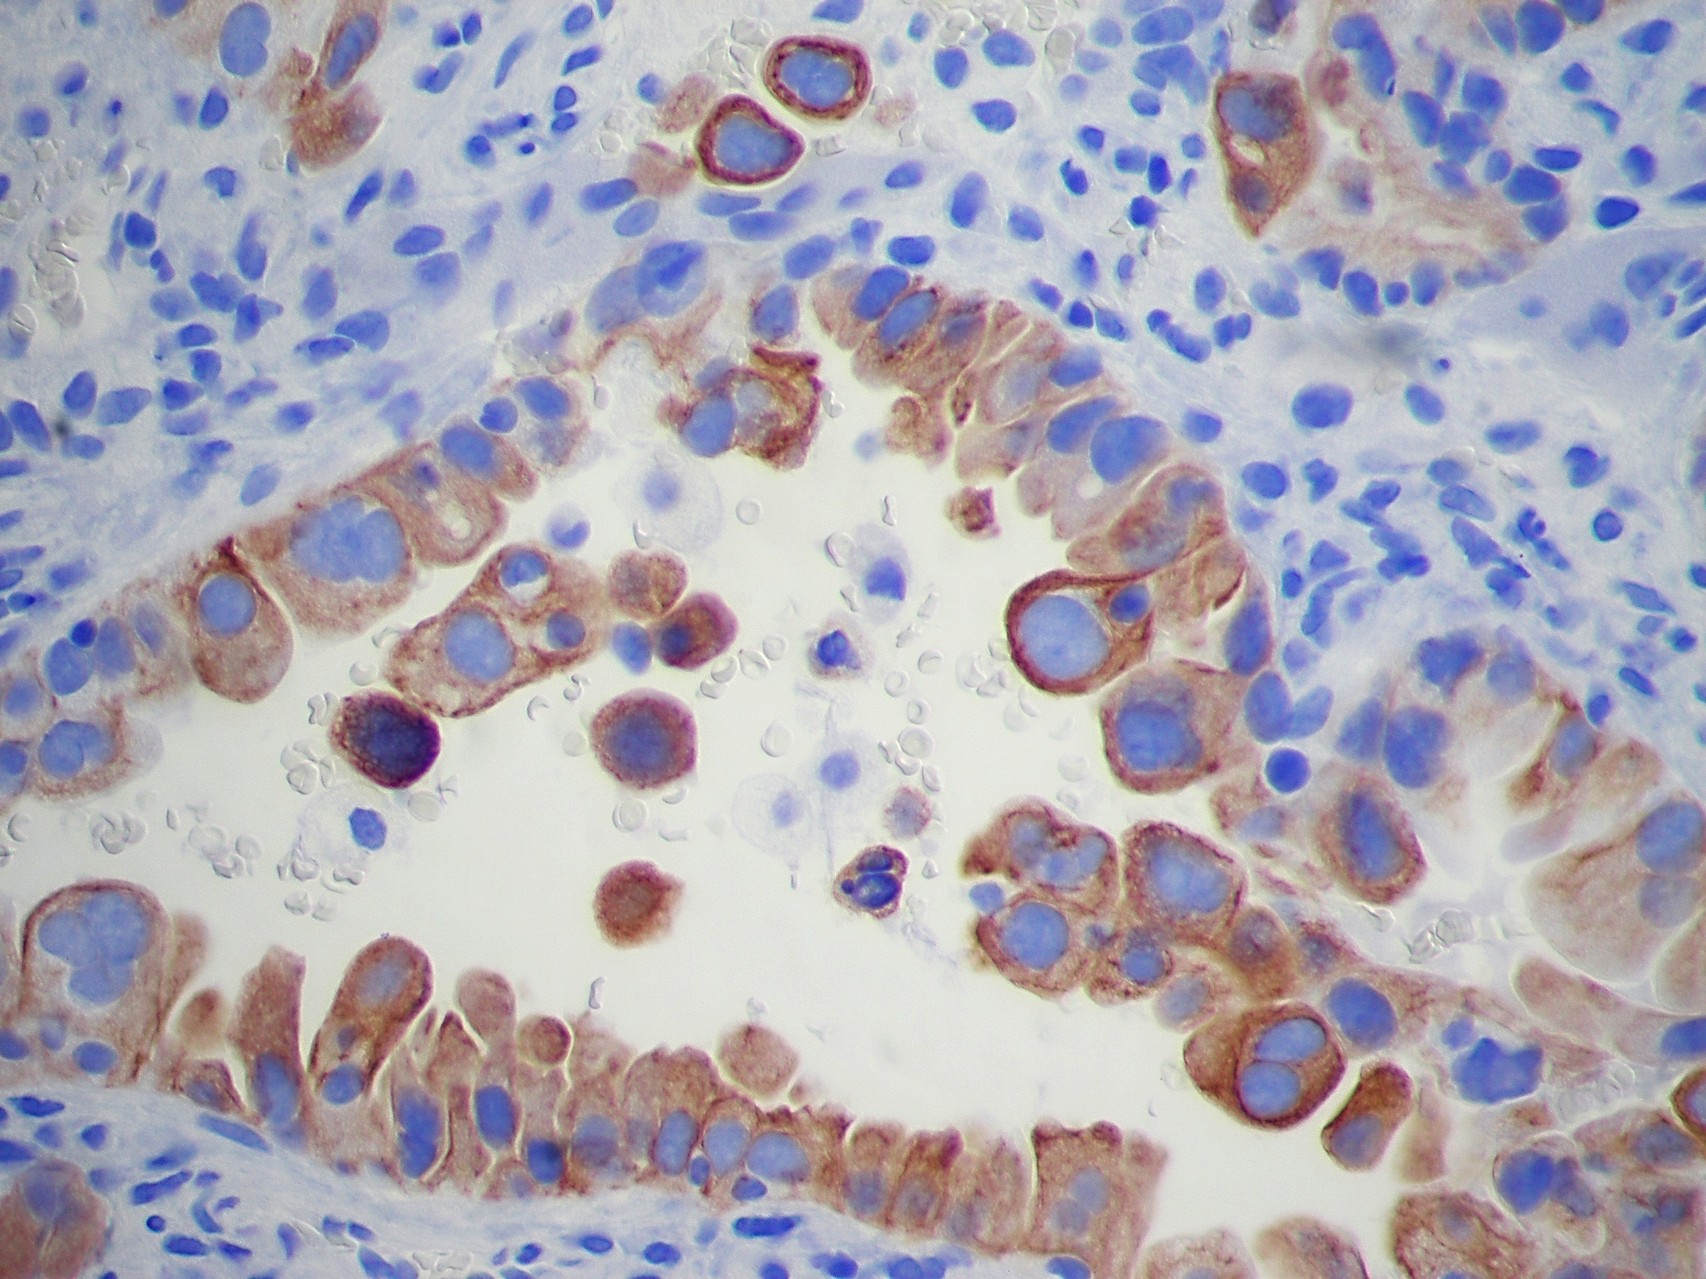

Patología Molecular

El diagnóstico sobre muestras de tejidos y líquidos corporales en plena era de la medicina del futuro, está basado en la integración de técnicas y conocimientos diferentes.

Hoy más que nunca es importante integrar una buena historia clínica con un correcto estudio de imagen y una buena morfología que además puede estar apoyada con proceso especiales complementarios relacionados con la Inmunología, Biología Molecular y Citogenética, generando así un estudio integral conocido como Patología Molecular.